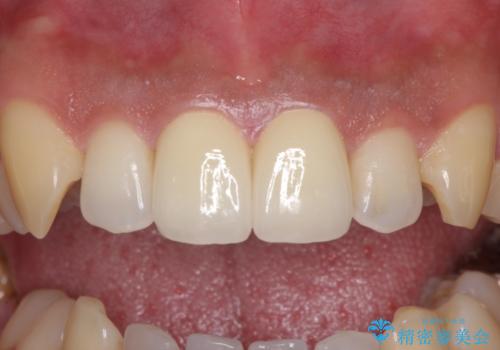

捻れた出っ歯の前歯 オールセラミッククラウンによる審美治療

1度の来院で進められる限りの処置を行ったため、4回の来院で僅か1ヶ月で治療を終えることができました。

気になっていた前歯の問題が解決し、患者様には大変満足していただきました。